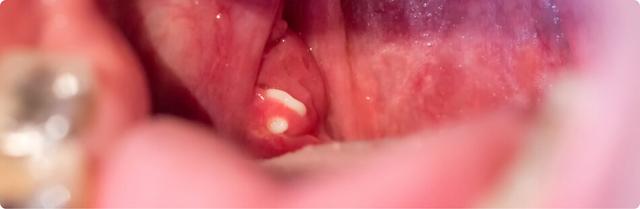

Mandelsteine sind weiß-gelbliche Ablagerungen von etwa drei bis vier Millimetern Größe. Ihre Konsistenz variiert von weich über krümelig bis steinhart. Sie können tief in den Krypten der Mandeln liegen oder an die Oberfläche gelangen. Mandelsteine können Mundgeruch verursachen und gelegentlich Beschwerden beim Schlucken oder einen Hustenreiz auslösen.

Mandelsteine sind kleine weiß-gelbliche Gebilde mit einer Größe von etwa drei bis vier Millimetern. Sie können weich, krümelig oder steinhart sein. Oft liegen sie tief in den Furchen der Gaumenmandeln verborgen, können aber auch an die Oberfläche gelangen und für unangenehmen Mundgeruch sorgen. Es ist wichtig zu beachten, dass Mandelsteine nicht mit den weißen Stippen einer akuten Mandelentzündung verwechselt werden sollten.

– Mandelsteine sind kleine weiß-gelbliche Gebilde mit einer Größe von etwa drei bis vier Millimetern.

– Sie können weich, krümelig oder steinhart sein und befinden sich oft tief in den Krypten der Gaumenmandeln.